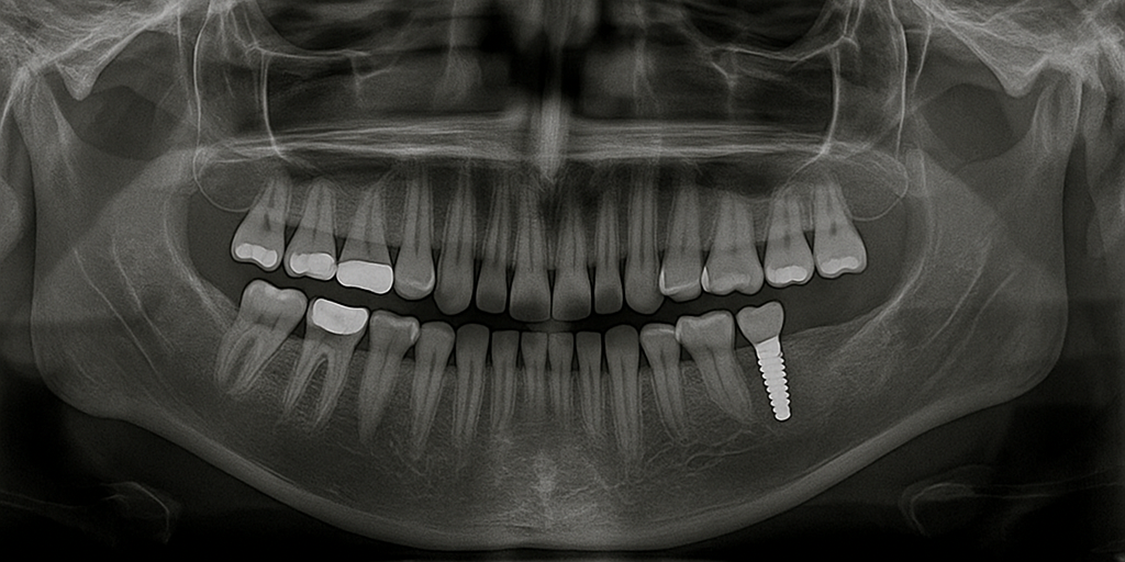

몇 년 전 오른쪽 아래 어금니를 빼고 임플란트를 심었습니다. 수술 전 CT 촬영으로 뼈 높이를 확인했고, 식립 후 3개월 정도 기다린 뒤 크라운을 올렸죠. 반면 왼쪽은 오래전에 브릿지로 치료했습니다. 양쪽을 쓰면서 치아 삭제, 씹는 느낌, 관리 난이도가 어떻게 다른지 몸으로 배웠습니다. 글의 기준은 이 체험에서 나왔습니다.

- 임플란트: 티타늄 픽스처가 잇몸뼈와 결합해 ‘인공 치근’이 생깁니다. 씹는 힘이 뼈로 전달되어 뼈가 유지되는 느낌이 있어요. 제 경우 오른쪽으로 고기 씹을 때 ‘쿡’ 하고 안정적으로 박히는 감각이 듭니다.

- 브릿지: 결손 부위를 사이에 두고 양 옆 치아를 깎아 연결 보철을 올립니다. 통증은 없었지만, 준비 단계에서 건강한 치아를 삭제한다는 점이 마음에 걸렸습니다. 다리 역할 치아가 피곤해지는 느낌을 관리로 상쇄해야 했습니다.